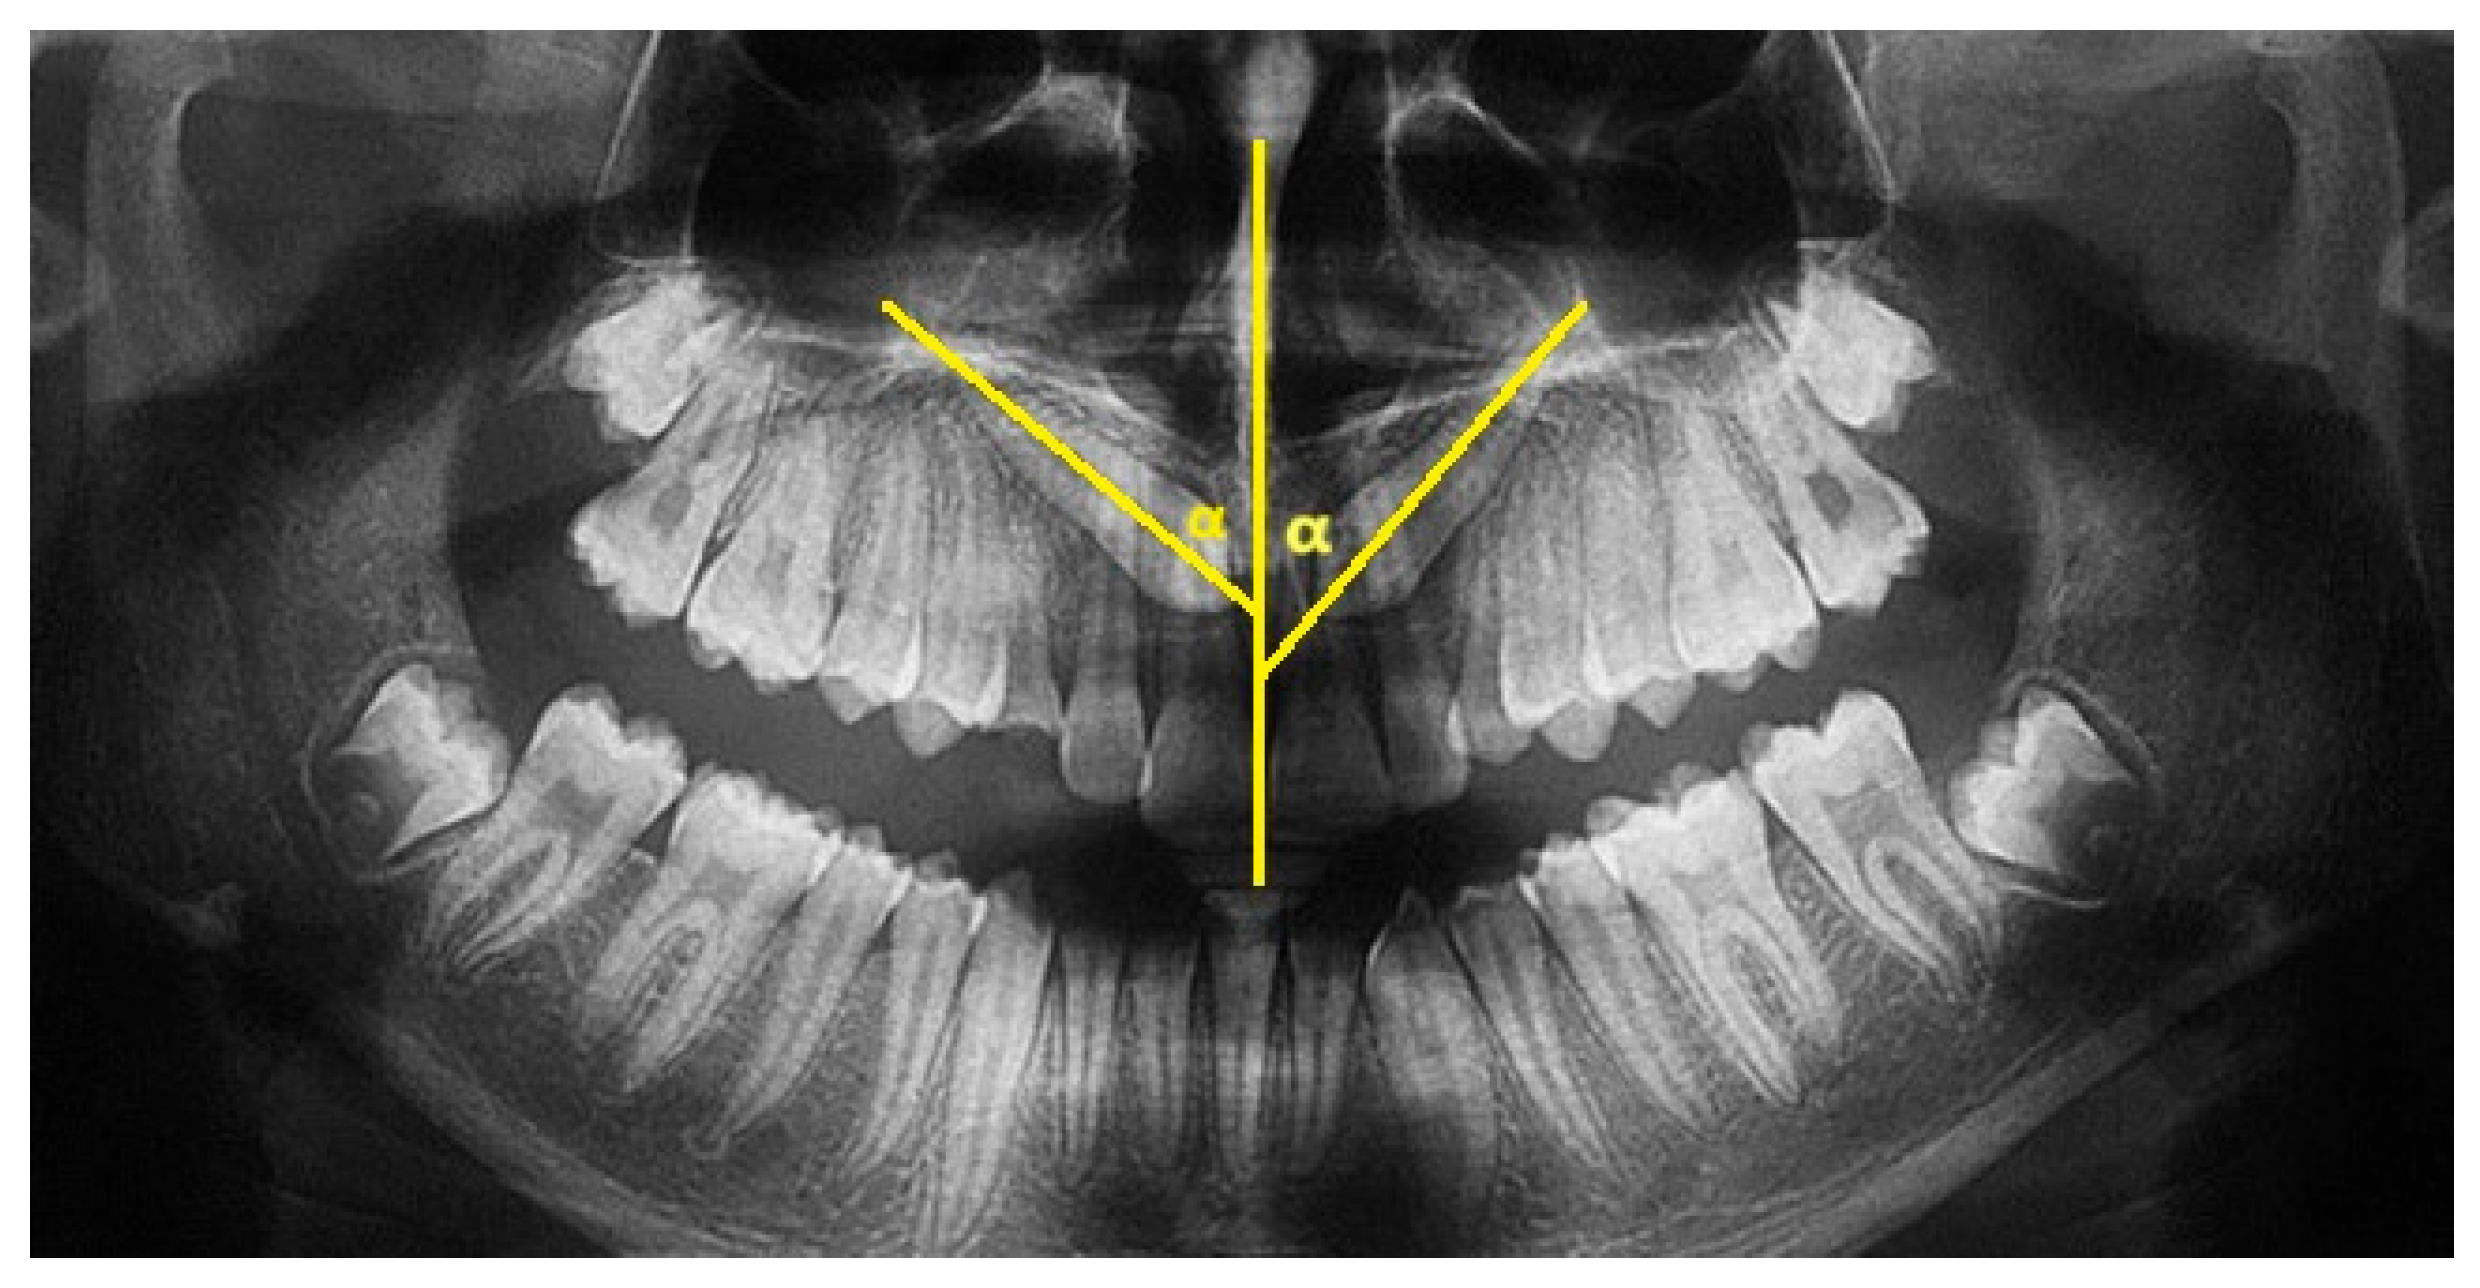

The major axis of the canine and the interincisor midline were traced on the panoramic X-ray. The angle between these two lines constitutes the inclusion angle α. The angulation of the canine with respect to the midline is generally considered to be mild if between 0° and 15°, moderate if between 16° and 30°, and severe if greater than 30° (Figure 1).

Figure 1.

Angle α of inclusion measured on OPT. The α angle of element 1.3 measures 48°; the α angle of element 2.3 measures 42°.